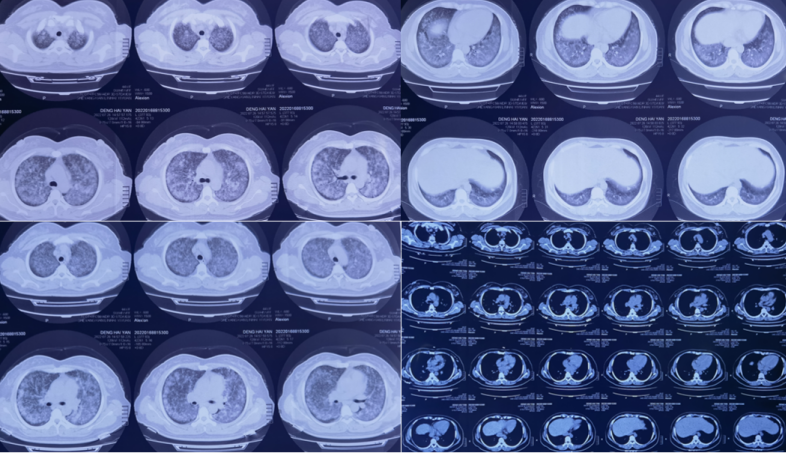

40岁女性患者,因“咳嗽、咳痰2月余,加重伴气喘20天”入院。无发热,无胸痛咯血,无下肢水肿。外院胸部CT示两肺感染。腺病毒IgM(+);CRP 34.1 mg/L;血气分析:pH 7.42,PaCO2 39 mmHg,PaO2 49 mmHg,SaO2 85%。常规抗病毒、抗感染治疗无效。

入院氧合指数<100 mmHg,感染指标基本正常,肿瘤指标无特殊异常,自身抗体阴性,病原学阴性。胸部CT示双肺大片实变渗出影,内可见支气管充气征图6

图片

图6  患者胸部CT

初步诊断:特殊病原体感染?急性纤维素性机化性肺炎?肺癌?淋巴瘤?